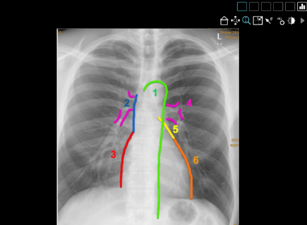

Für die Nutzung der CoRad-19-Kurse bedarf es keiner extra Software: Ein PC mit einer Internetverbindung reicht aus, um mittels der interaktiven fallbasierten Lehrmodule neues Wissen zu erwerben, es praxisnah anzuwenden und zu erweitern. Von Neuroradiologie über Muskuloskelettale Radiologie bis hin zur Interventionellen Radiologie decken die zehn Kurse aus dem CoRad-19-Angebot das gesamte Themenspektrum der radiologischen Ausbildung ab. Die Kursinhalte und Fallsammlungen wurden von sieben Experten aufgearbeitet: Dr. Saif Afat (Tübingen), Priv.-Doz. Dr. Bettina Baeßler (Zürich), Dr. Nienke Hansen (Köln), Dr. Katharina Müller-Peltzer (Freiburg), Priv.-Doz. Dr. Ahmed Othman (Tübingen), Dr. Daniel Pinto dos Santos (Köln), Dr. Fabian Rengier (Heidelberg).